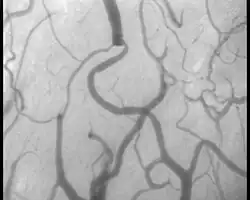

Sidestream Dark Field Imaging

On appelle Sidestream Dark Field Imaging (SDF, imagerie en champ sombre avec éclairage de côté) un procédé d'étude de la microcirculation sanguine, c'est-à-dire l'étude des petits vaisseaux sanguins, jusqu'aux plus petits. Le procédé est appliqué avec un appareillage qui permet d'étudier ces vaisseaux chez les patients, par exemple sous la langue, où il n'y a pas de couches de peau gênantes. La technique utilise un guide de lumière central, dans lequel une lentille projette l'image de l'échantillon sur un capteur photographique numérique. La lumière de photodiodes vertes (longueur d'onde de 530 nm) est projetée sur l'échantillon à partir d'un anneau autour du guide de lumière central[22],[23]

La diffusion dans l'échantillon amène une distribution homogène de la lumière dans la zone observée, si bien qu'une sorte d'éclairage de fond a lieu. L'hémoglobine dans les globules rouges absorbe très fortement la lumière verte, si bien que les vaisseaux sanguins remplis de nombreux globules rouges se détachent comme des structures sombres sur un fond plus clair. La profondeur maximale de pénétration dans le tissu se situe à environ 0,5 mm[22],[23].